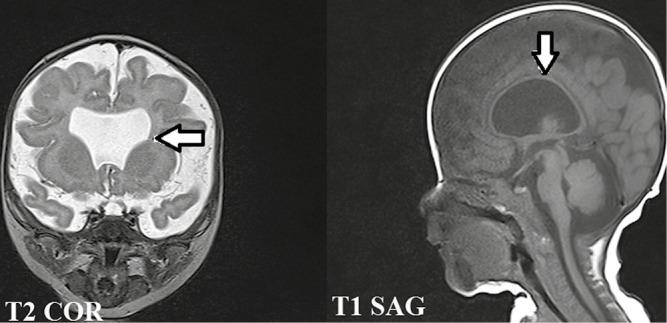

Septo-optic Dysplasia with Cerebellar Hemiagenesis.

A 1-month-old girl child, who was found to have hydrocephalus on prenatal ultrasound, was postnatally evaluated with magnetic resonance imaging (MRI) of brain, which showed two classical findings of septo-optic dysplasia (SOD), namely optic nerve hypoplasia and absent septum pellucidum. In addition, the patient was found to have cerebellar hemiagenesis.